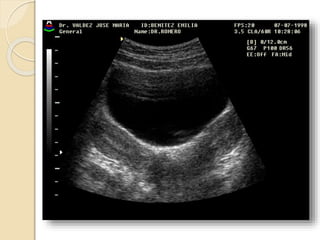

Masas Ováricas Neoplásicas

Masa ovárica sospechosa

de malignidad:

1. Masa liquida sólida-liquida

2. Pared gruesa

3. Pared irregular

4. Septo grueso

5. Proyecciones papilares

6. Masa sólida

La presunción de un proceso

maligno esta dada por la

invasión de órganos vecinos,

adenomegalias pélvicas o

retroperitoneales, ascitis,

metástasis, uronefrosis, etc.

Es importante mencionar que

para los tumores limitados al

ovario la curación excede el

85%, los tumores con extensión

al abdomen o fuera del mismo

tiene una sobrevida a 5 años

menor al 15%.